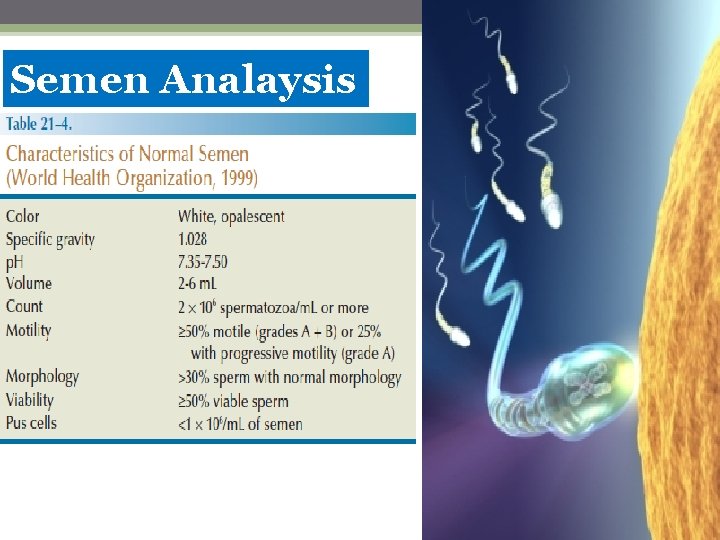

Semen Analaysis